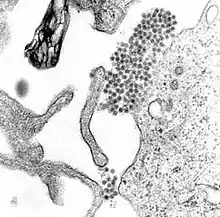

L'agent est le virus de la dengue, un virus à ARN enveloppé, appartenant au genre des flavivirus. Ce genre comprend également les virus de la fièvre jaune, de l'encéphalite japonaise, et du Nil occidental.

Il existe quatre sérotypes distincts du virus de la dengue : DENV-1, DENV-2, DENV-3 et DENV-4[13]. Ils sont étroitement apparentés et entraînent les mêmes signes cliniques.

Les virus sont transmis par moustiques vecteurs du genre Aedes.